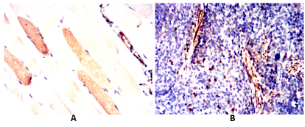

| AC1972 | CNN1 Mouse Monoclonal antibody[1H5B5] | 100ug | $367 | 10days |

| AC1972 | CNN1 Mouse Monoclonal antibody[1H5B5] | 200ug | $660.6 | 10days |